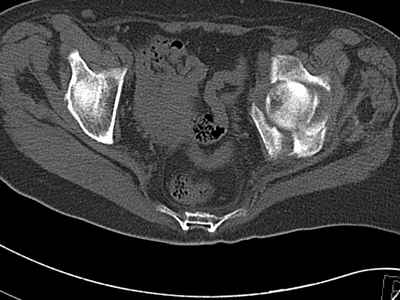

Уважаемые коллеги, возник вопрос по лечению нашей пациентки 60 лет. Около года назад множественная травма: в том числе Т-образный перелом вертлужной впадины.

На сегодняшний день сращение отломков имеется на ограниченных участках, имеется дефект задней колонны вертлужной впадины. Движения неплохие, ходит с костылями, приступая на ногу.

По мнению эдопротезистов при установке антипротрузионного кольца или октопуса не хватит костного материала и необходимо перед протезированием выполнить реконструкцию впадины, иначе чашка протеза неминуемо выпадет.